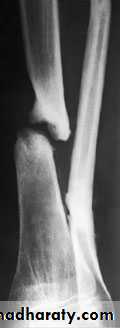

3-Non-union This may follow bone loss or deep

infection, but a common cause is faulty treatment.

Hypertrophic non-union can be treated by intra -

medullary nailing (or exchange nailing) or compression

plating. Atrophic non-union needs bone grafting also.

Non union